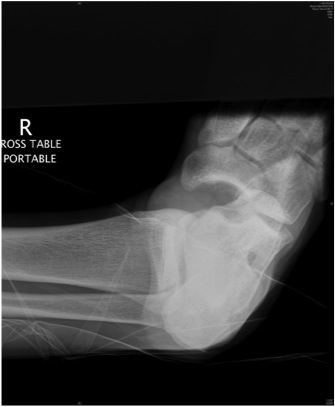

Subtalar Dislocation

Epidemiology

Rare

Types

Medial

- 80%

- calcaneum dislocated medially

Lateral

- 20%

- higher energy injury